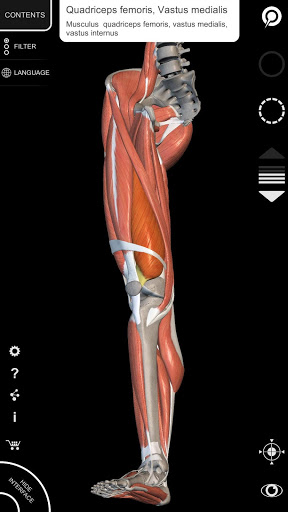

"Anatomía - Atlas 3D" permite estudiar la anatomía humana de forma fácil e interactiva.

A través de una interfaz sencilla e intuitiva es posible observar cada estructura anatómica desde cualquier ángulo.

Los modelos anatómicos 3D son especialmente detallados y con texturas de hasta una resolución de 4k.

La subdivisión por regiones y las vistas predefinidas facilitan la observación y el estudio de partes individuales o grupos de sistemas y las relaciones entre los diferentes órganos.

MODELOS ANATÓMICOS 3D

• Sistema musculoesquelético

nervioso • Sistema respiratorio • Sistema digestivo • Sistema urogenital (masculino y femenino) • Sistema endocrino • Sistema linfático • Sistema ocular y auditivo CARACTERÍSTICAS • Interfaz sencilla e intuitiva • Rotar y hacer zoom en cada modelo en el espacio 3D • Opción para ocultar o aislar uno o varios modelos seleccionados • Filtro para ocultar o mostrar cada sistema • Función de búsqueda para encontrar fácilmente cada parte anatómica • Función de marcador para guardar vistas personalizadas • Rotación inteligente que mueve el centro de rotación automáticamente • Función de transparencia • Visualización de músculos a través de niveles de capas desde las superficiales hasta las más profundas • Al seleccionar un modelo o un pin, aparece el término anatómico relacionado • Descripción de los músculos: origen, inserción, inervación y acción • Mostrar/ocultar interfaz de usuario (muy útil con pantallas pequeñas) MULTILINGÜE • Los términos anatómicos y la interfaz de usuario están disponibles en 11 idiomas: latín, inglés, francés, alemán, italiano, portugués, turco, ruso, español, Chino, japonés y coreano • Los términos anatómicos se pueden mostrar en dos idiomas simultáneamente REQUISITOS DEL SISTEMA • Android 8.0 o posterior, dispositivos con al menos 3 GB de RAM Reversi